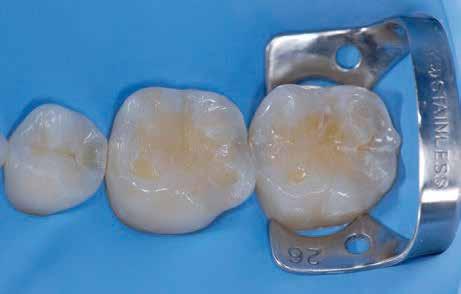

1a 1c 1b 1d

1. a-d ábrák: a) Fogerózió a molárisok okkluzális felszínén, b) maratás foszforsavval, c) minimálisan invazív műgyanta-kompozit fedőréteg levegővel történő felszívása, d) adhezív ragasztott fedőréteg a hiányzó zománc és dentin helyreállítására.